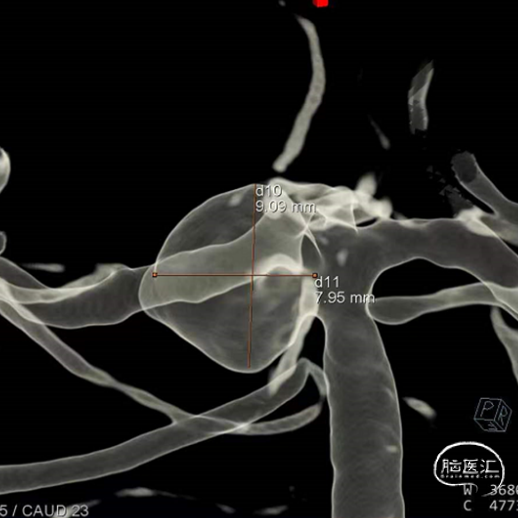

经测量可得动脉瘤宽度平均值为9.1mm,动脉瘤最小高度为8.9mm,最终选择WEB™ SL 11*6。